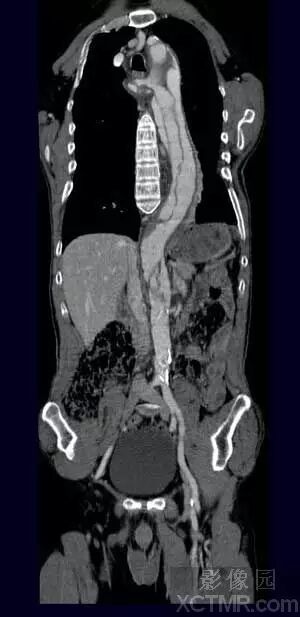

泌尿系统

VR图像可以清晰地显示经对比剂强化的肾脏、肾盏和肾盂的完整形态,以及全程输尿管的走行和梗阻、狭窄部位和狭窄程度,并能以多角度直观地显示肾脏、输尿管与周围血管以及骨骼之间的解剖关系。

VR在泌尿系统疾病的检查中,可以通过去骨、剪切、旋转来显示肾盂、输尿管、膀胱,也可以保留脊椎、骨盆,也可以将泌尿系统的器官和骨骼用不同的颜色区别开。肿瘤应用VR多曲线调整(Free setting Multi-Threshold values Curve)技术可以将经对比剂强化的各系统和器官的肿瘤在同一幅三维图像上同时获得骨、血管和软组织的影像,能够对肿瘤准确地定位、完整地显示病灶本身的状态以及与周围组织器官和血管的毗邻关系和受侵及、挤压移位等情况。经处理后的图像可以对病变进行任意角度的旋转,多方位观察和分析。为了清晰地显示病灶的隐蔽部分,可对图像进行剪裁、切割、钻洞和制作自动电影,为临床医生对疾病做出正确的判断提供更加丰富的影像学信息。

同样病例VR图象显示结石不如MIP显示清楚。

MIP比VR显示髂动脉钙化更加清晰。